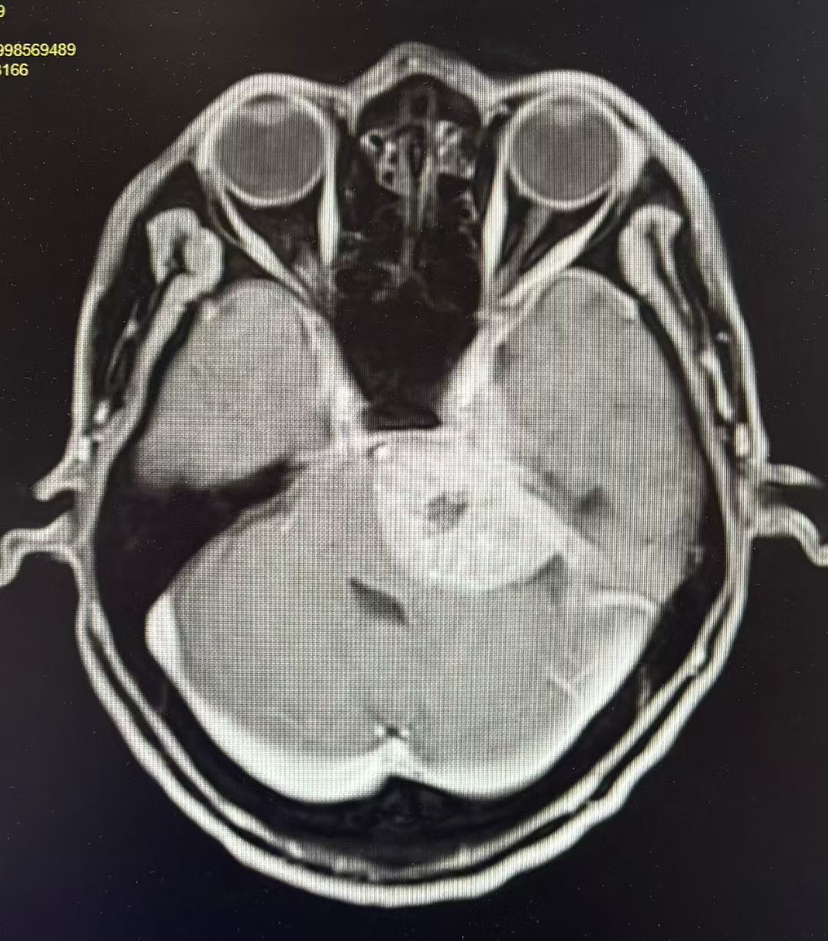

术前MRI